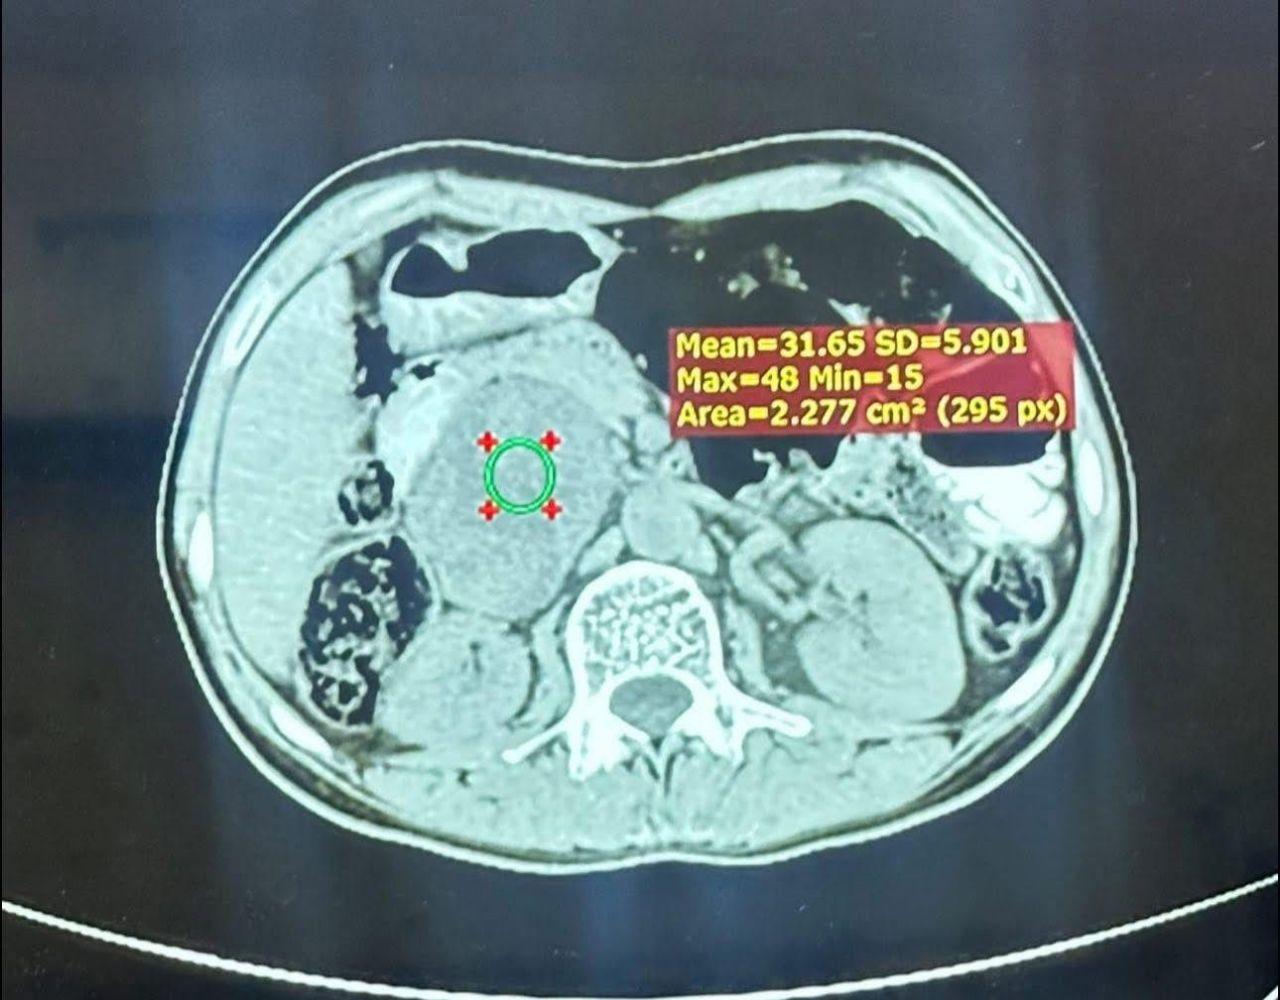

وذكر المبارك ان المريض البالغ من العمر ٢٥ عامًا والذي يسكن محافظة نينوى احيل إلى مركز الفيحاء التخصصي بعد ملاحظة ارتفاع شديد في ضغط الدم وتسارع حاد في ضربات القلب، وبعد إجراء الفحوصات اللازمة، تبيّن وجود ورم كبير في الغدة الكظرية اليمنى، يفرز كميات مرتفعة جدًا من هرمون الأدرينالين (Pheochromocytoma)، والذي يشكّل خطرًا كبيرًا على حياته، وأظهرت الفحوصات أن الورم كان مخترقًا من الأوعية الدموية الرئيسية، مما زاد من تعقيد وخطورة التداخل الجراحي.